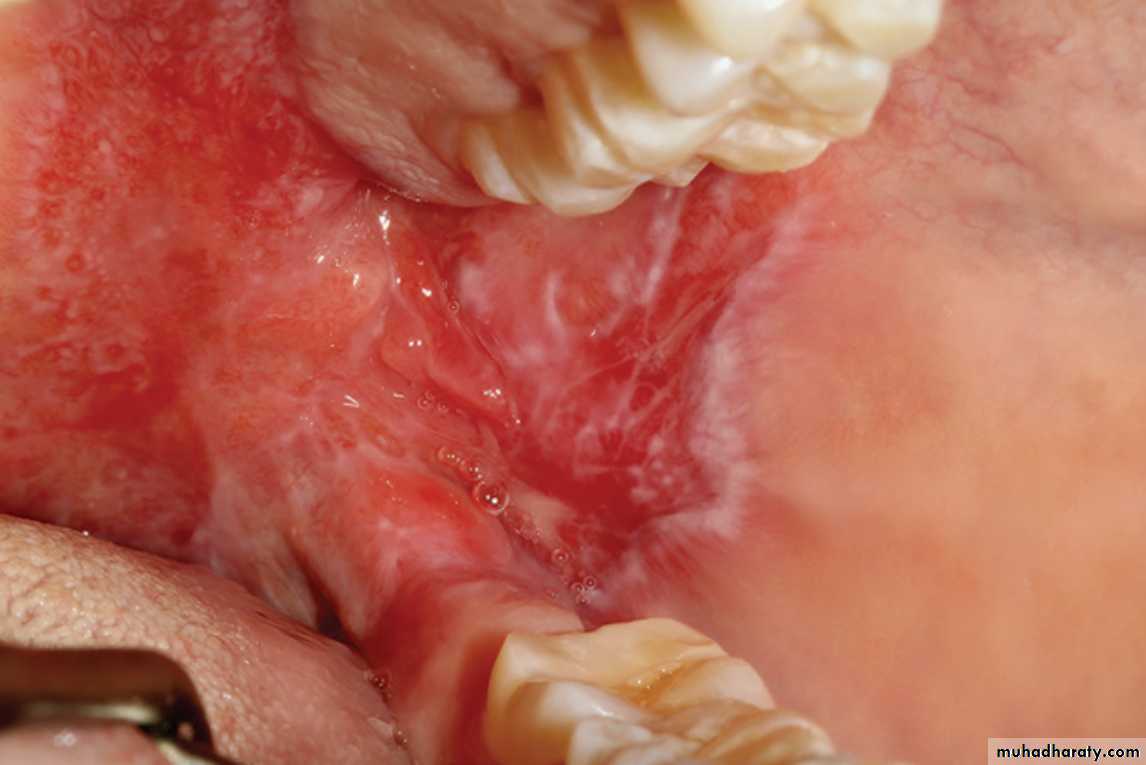

Oral lesions of LE

SLE. This ulceration of the buccal mucosa exhibits fine radiating white striae at its periphery, clinically appearing similar to erosive lichen planus

Atrophic lesion with radiating striae, on the buccal mucosa. Such a lesion as here, LE. The clinical presentation is often very similar to LP, therefore, should be investigated for both LP & LE•

DLE. Radiating keratotic striae surrounding an erythematous zones of the buccal mucosa. These features are similar to those of erosive lichen planus•

LE. Oral mucosal lesions often appear similar to those of lichen planus, showing areas of erythema in conjunction with white plaques and striae affecting the buccal mucosa